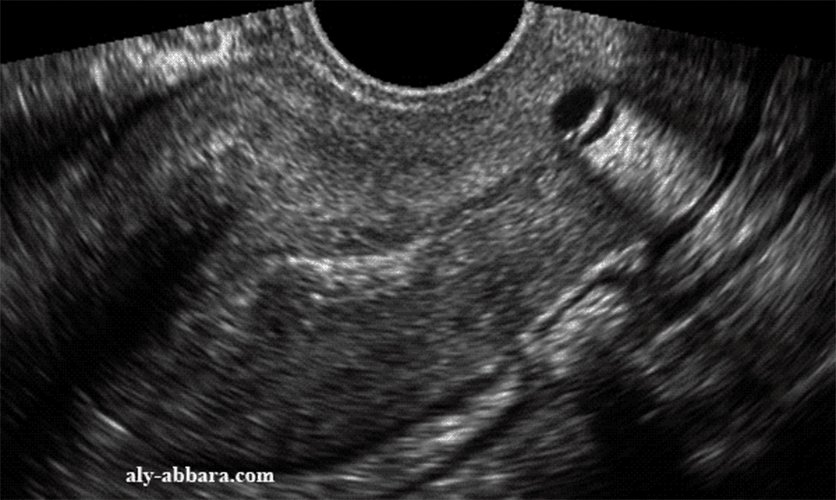

Les complications après l'ablation d'un polype sont rares, mais peuvent inclure des infections ou des saignements abondants Un signe de cela est une douleur ou une odeur provenant de la région. Après l'élimination des polypes, la fièvre peut rester pendant un certain temps

Polipii uterini cauze, simptome și tratament Fetal Care. La plupart des polypes sont bénins, mais ils peuvent devenir malins avec le temps. L'ablation des polypes par ablation de l'endomètre consiste à retirer la muqueuse qui facilite la croissance du fœtus, selon John Hopkins Medicine